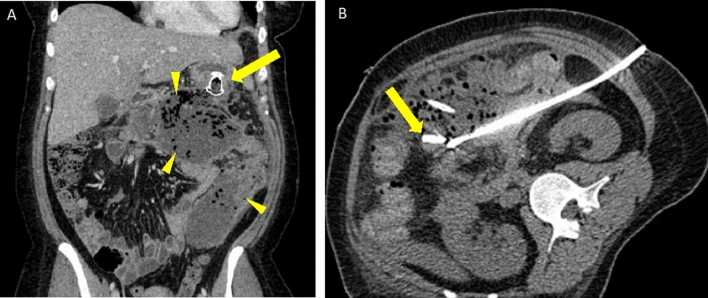

Fig. 13.

Gas within necrotizing pancreatitis collections due to infection. A Axial PO and IV contrast-enhanced CT showing a patient with NP with a small amount of gas in WON near the pancreatic head (arrow). No extraluminal contrast was seen to indicate bowel perforation. This patient required percutaneous drainage due to infection. B Axial non-contrast CT shows extensive gas within a large infected ANC replacing the pancreas. Percutaneous and endoscopic drainage were pursued in this patient, but ultimately surgical retroperitoneal debridement was required